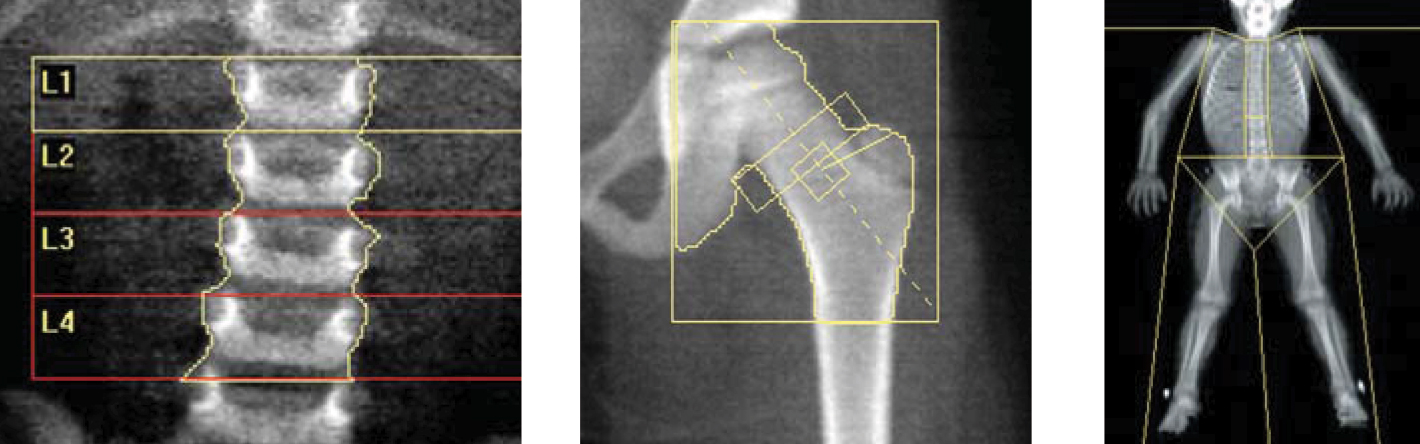

Kemik yoğunluğu ölçimi çok kolay bir işlemdir.Kişi sırt üzeri yatarken sistem 8 dk.gibi kısa bir sürede ölçümü gerçekleştirmektedir. Kliniğimizde kemik yoğunluğu ölçümü son teknoloji General Electric/LUNAR markacihazımızda yapılmaktadır.

En önemli tanı yöntemi kemik yoğunluğu ölçümüdür. İnceleme çok düşük dozda röntgen ışını kullanılarak özel bir cihozla yapılır. İşlem ön hazıriık veya ilaç gerektirmez, kısa sürer.

Kemik yoğunluğu ölçümü ünitemizde bilgisayar desteğinde hiçbir ön hazırlık yapılmadan, hiçbir enjeksiyon yapılmadan 10-20 dakikada yapılmaktadır.